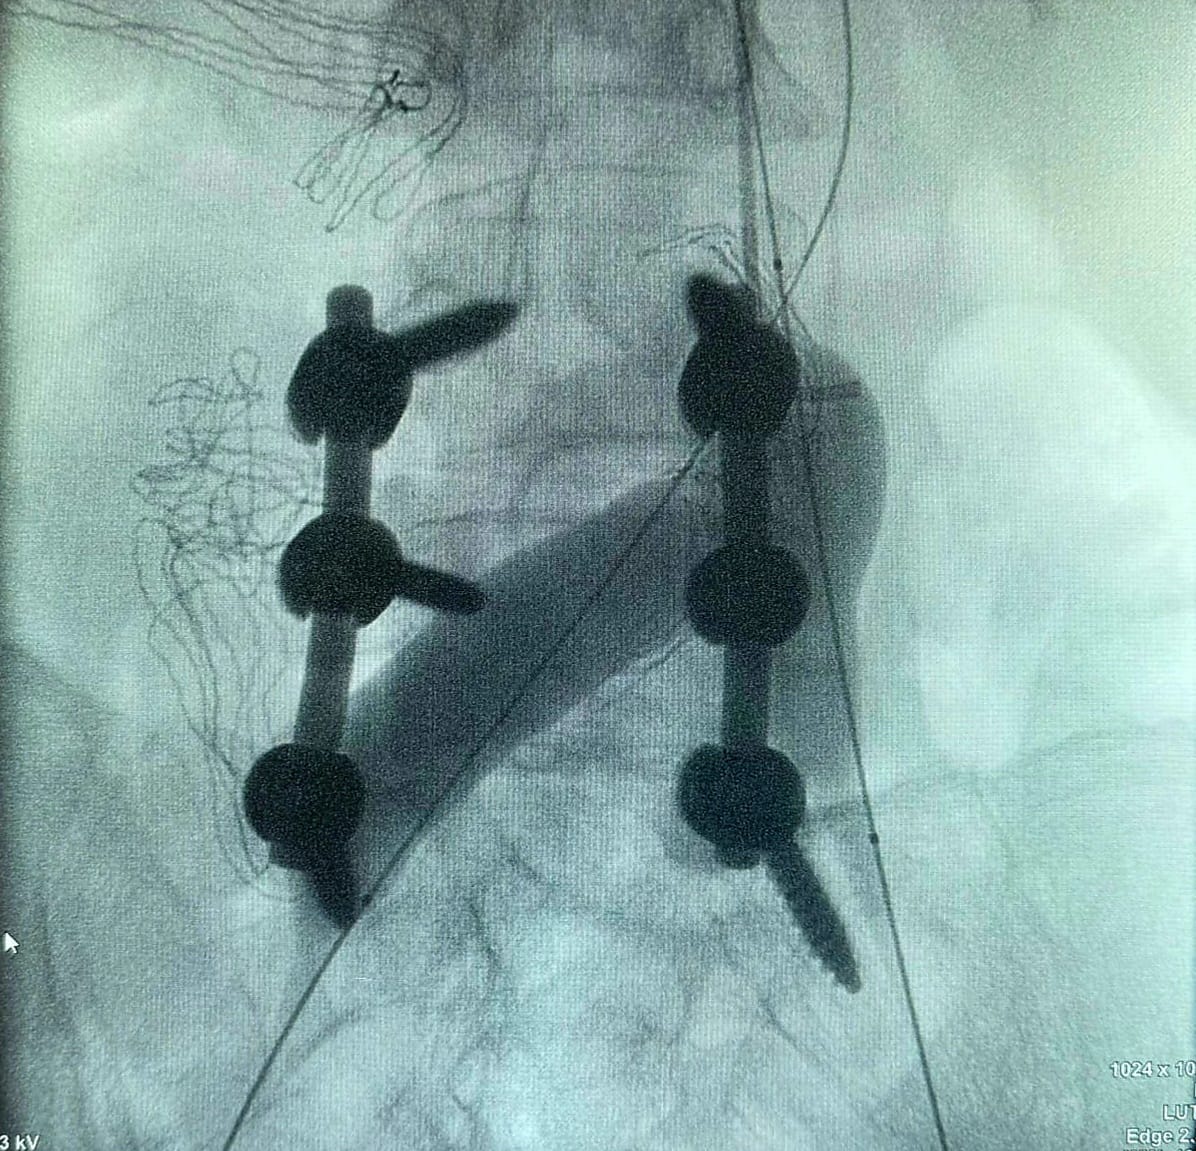

La revisione dell’impianto presentava un rischio elevatissimo: le viti peduncolari precedentemente inserite oltrepassavano il corpo vertebrale, penetrando nella pelvi e andando in conflitto con le vene iliache bilaterali. La loro rimozione avrebbe potuto provocare una grave emorragia intra-addominale.

Per questo è stata pianificata una strategia combinata. Per via transfemorale, la Radiologia Interventistica ha posizionato due palloni endovascolari nelle vene iliache, con funzione emostatica preventiva. Contestualmente, per via transgiugulare, è stata eseguita una flebografia di controllo con mezzo di contrasto per escludere sanguinamenti attivi. Durante tutta la procedura, la Chirurgia Vascolare ha garantito monitoraggio costante e pronta disponibilità in caso di complicanze.